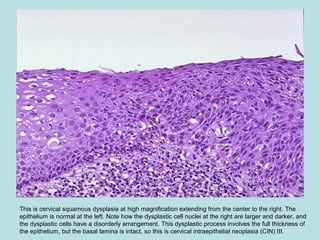

This is cervical squamous dysplasia at high magnification extending from the center to the right. The

epithelium is normal at the left. Note how the dysplastic cell nuclei at the right are larger and darker, and

the dysplastic cells have a disorderly arrangement. This dysplastic process involves the full thickness of

the epithelium, but the basal lamina is intact, so this is cervical intraepithelial neoplasia (CIN) III.